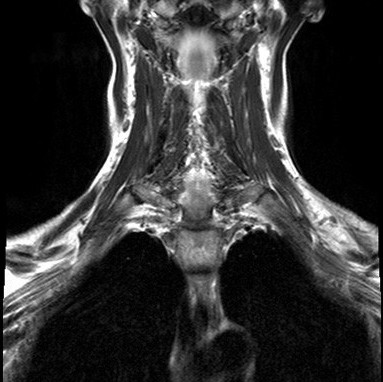

Для оценки распространенности липомы гортани (в случае ее больших размеров) используются:

- рентгенография черепа;

- ультразвуковое исследование (УЗИ);

- компьютерная томография (КТ);

- магнитно-резонансная томография (МРТ).